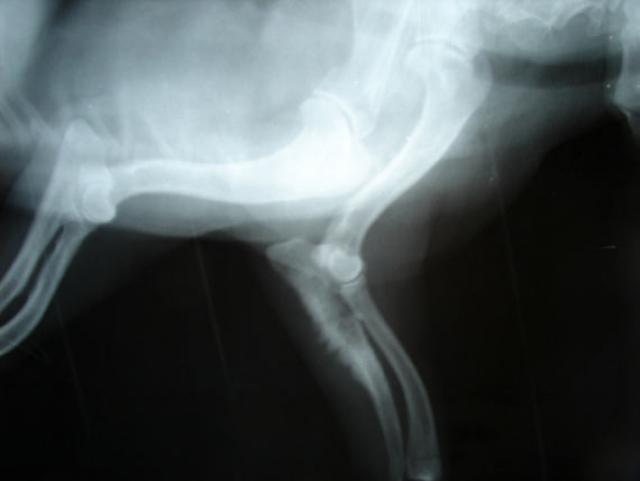

I rely on the advanced diagnostic tools that are so readily available to me to help achieve a definitive answer as to what is causing a particular pet’s illness and to help perform what are known as staging tests for various cancers. Staging refers to examining where in the body the cancer can be found, and many tumor types have a specific staging scheme, which is often found to correlate with prognosis. The results of staging tests will influence treatment recommendations. For example, in cases where tumors are localized to a single anatomical area of the body, I will often recommend a localized form of treatment such as surgery and/or radiation therapy. However, in cases where the cancer is more widespread, I will typically recommend systemic therapy (e.g., chemotherapy or immunotherapy).

For example, sometimes pets will undergo an ultrasound test at their regular veterinarian’s office as part of a diagnostic work-up for chronic vomiting, and the scan will reveal a tumor within an intra-abdominal organ. The animal then has surgery to remove the tumor, and a diagnosis of cancer is confirmed on a biopsy. Owners are typically then referred to see me in order to discuss various treatment options for the tumor. In most cases, I recommend that a repeat post-operative ultrasound be performed fairly soon after surgery to provide a baseline before starting treatment, and that recheck exams be performed every three months or so for at least the first year following the diagnosis.

The initial recheck exam is very important because structures and organs will look differently after surgery when compared to the pre-operative scan. If a portion of the gastrointestinal tract was removed, this can be detected on the scan and that particular region of the tract will appear differently. The scan provides new information from which future comparisons can be made and eliminates the question of “Was this abnormality present after surgery?” that is asked several months down the line when the next scan is performed. If owners cannot afford the post-operative ultrasound, we will postpone this test until later in the treatment plan, with a full understanding that though not ideal, we are still providing the pet with its best chance for survival in the long run.